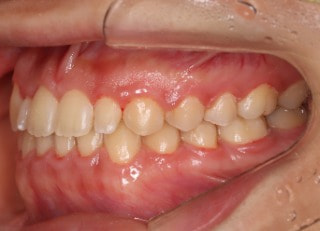

症例紹介

上顎2番矮小歯右下2番先天欠如

解説:下顎前突上顎劣勢長傾向で、上顎両側2番が矮小歯、右下2番先天欠如症例なので、上下前歯の幅径の比率を調節する必要があるケースです。(ご本人のご都合で治療中に来院できない期間がありました)

治療前